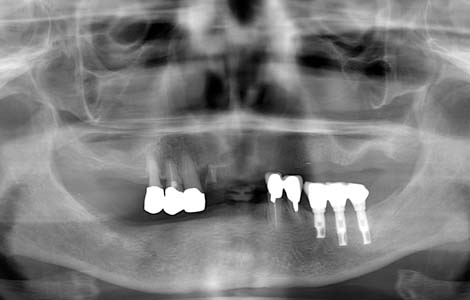

すれ違いはインプラント

入れ歯を外した時に、上下の歯が1箇所も噛み合わない状態を、「すれ違い咬合」と呼びます。この様な状態の方に入れ歯を作っても、噛むたびに歯がない方が大きく沈み込んしまうため、入れ歯ががたつき満足してもらえることはありません。この症例では、下の入れ歯を何度作っても痛くて噛めないという訴えでした。右下に傷がありました。

インプラントで入れ歯の沈みこみを抑える

解決策は、歯を抜いて総入れ歯にすることで入れ歯の沈みこみを均等にするか、インプラントを入れて入れ歯の沈みこみを抑えるようにするしかありません。この症例では右下に2本のインプラントを入れました。これで右下の入れ歯の沈みこみが防げるようになったので、痛みもなくお食事ができるようになりました。